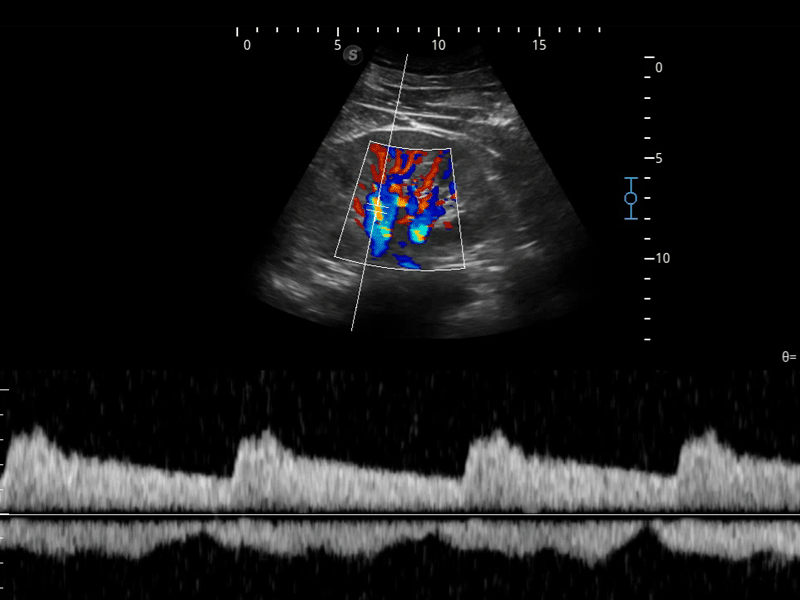

開立醫(yī)療通過不斷的技術(shù)創(chuàng)新,為大眾的生命健康提供持續(xù)關(guān)愛。P12 Plus采用全新一代超聲成像平臺,新平臺旨在將真實還原組織解剖結(jié)構(gòu)作為首要目標(biāo)。平臺采用全新集成化硬件模塊,搭載新一代芯片,系統(tǒng)性能得到大幅提升,為您的診斷提供了豐富的臨床信息。優(yōu)異的圖像表現(xiàn),豐富的探頭配置,全面的應(yīng)用功能,為您日常診斷提供了可靠的助手。

彩色多普勒超聲診斷系統(tǒng)